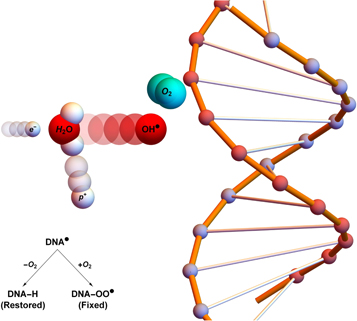

) which in turn cause DNA base damage. In general, this kind of radical damage is readily chemically repaired. However, when these radicals encounter molecular oxygen they form a peroxyl radical, RO2 This is much more damaging, difficult or impossible to for the cell to repair. In essence, damage produced by free-radicals can be restored under hypoxia but is 'fixed' (made permanent and irreparable) when molecular oxygen is present [12, 13], as illustrated in figure 1.

This is much more damaging, difficult or impossible to for the cell to repair. In essence, damage produced by free-radicals can be restored under hypoxia but is 'fixed' (made permanent and irreparable) when molecular oxygen is present [12, 13], as illustrated in figure 1.

Figure 1. Oxygen fixation hypothesis—a high energy electron created by an x-ray photon ( ) impinges upon a water molecule, liberating a proton (

) impinges upon a water molecule, liberating a proton ( ) and creating a hydroxyl radical (OH

) and creating a hydroxyl radical (OH ). This reactive molecule then impacts upon DNA, resulting in ionization damage, DNA

). This reactive molecule then impacts upon DNA, resulting in ionization damage, DNA This can be readily repaired to its original state (DNA-H), but in the presence of molecular oxygen a peroxy radical is formed (DNA-OO

This can be readily repaired to its original state (DNA-H), but in the presence of molecular oxygen a peroxy radical is formed (DNA-OO ), 'fixing' damage into a permanent irreparable state.

), 'fixing' damage into a permanent irreparable state.